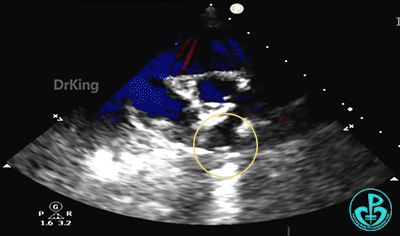

完全释放后超声下观察

主动脉短轴切面显示封堵器呈Y字型抱住主动脉根部,夹持稳定。

封堵器形态良好,未见分流,封堵成功。

2. 该患儿缺损部位紧邻主动脉根部,使用金属封堵器进行封堵可能增加封堵器与主动脉根部之间的接触风险,对主动脉造成压迫,引发组织磨蚀、血栓等长期并发症。基于孩子远期健康的考量,本例患儿选择了可降解封堵器进行封堵。可降解房间隔缺损封堵器专利成型锁定设计,可确保封堵器稳定夹持主动脉根部;同时其贴壁、贴合效果好,锁定后封堵器紧密贴合于缺损部位利于内皮化,使其在封堵靠近主动脉根部等复杂房缺治疗中临床优势显著。